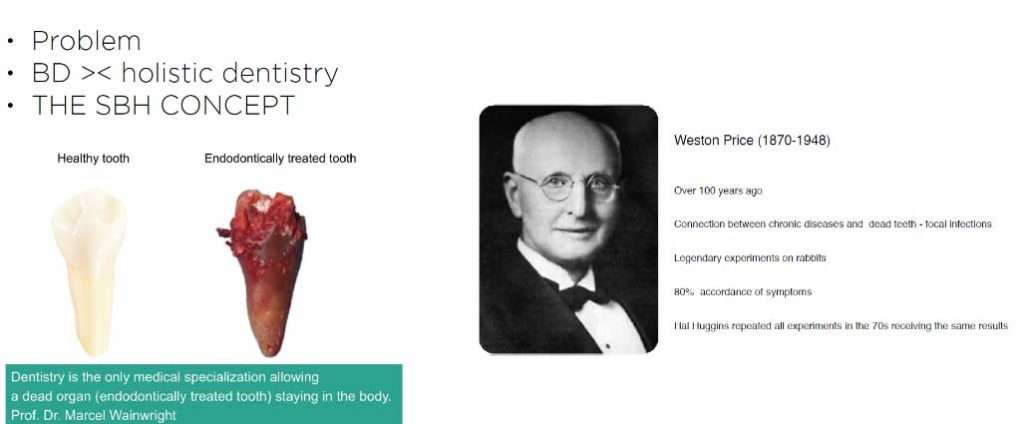

The problem with root canal therapy is it is a flawed therapy, the intention behind doing it is to be able to fully sterilize a tooth which no longer revives blood supply, nerve supply, lymph drainage or any signs of so called life. Anything that is non-vital is usually energetically a break in the circuit. This is the reason why people who have multiple root canal treated teeth complain of chronic fatigue, insomnia as some of the presenting symptom. Any non-vital part of the body is the breeding ground for gram negative anaerobic bacteria and the toxins from this low grade chronic inflammation(silent inflammation) activates the immune system. People with multiple root canal treated teeth usually present with some form of autoimmune condition on their health history.

The problem with root canal therapy is it is a flawed therapy, the intention behind doing it is to be able to fully sterilize a tooth which no longer revives blood supply, nerve supply, lymph drainage or any signs of so called life. Anything that is non-vital is usually energetically a break in the circuit. This is the reason why people who have multiple root canal treated teeth complain of chronic fatigue, insomnia as some of the presenting symptom. Any non-vital part of the body is the breeding ground for gram negative anaerobic bacteria and the toxins from this low grade chronic inflammation(silent inflammation) activates the immune system. People with multiple root canal treated teeth usually present with some form of autoimmune condition on their health history.